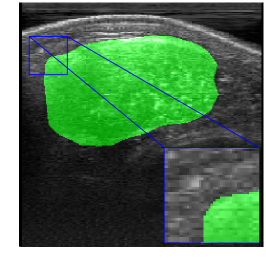

Rib Eye Area (REA). This image dataset consists of ultrasound images of the Longissimus dorsi muscle between the 11th and 13th ribs of cattle. The goal is to automatically calculate the rib eye area (REA), an important region for decision making during cattle breeding. The main challenge is the uncertainty in the REA annotation, since the image is noisy and even experts have difficulty in delimiting the borders of this region. Fig. 3 presents examples of images and the annotation made by a specialist. We can observe that some borders are absent and depend on the subjectivity and knowledge of the annotator. To evaluate the segmentation methods, 76 images with resolution were obtained and labeled by an expert. Due to the number of images, the division of the images in training and testing followed 5-fold cross-validation.

REA dataset. This image dataset has high uncertainty during labeling due to noise from the ultrasound image. In some cases, the border of REA is not completely visible and must be estimated by the specialist. Therefore, the proposed approach becomes essential to obtain accurate segmentation at the edges. The segmentation examples in Fig. 6 show that the baseline was not able to define the REA correctly due to the uncertainty of the labeling. On the other hand, the proposed approach presents results close to the specialist in regions that the border needs to be estimated.